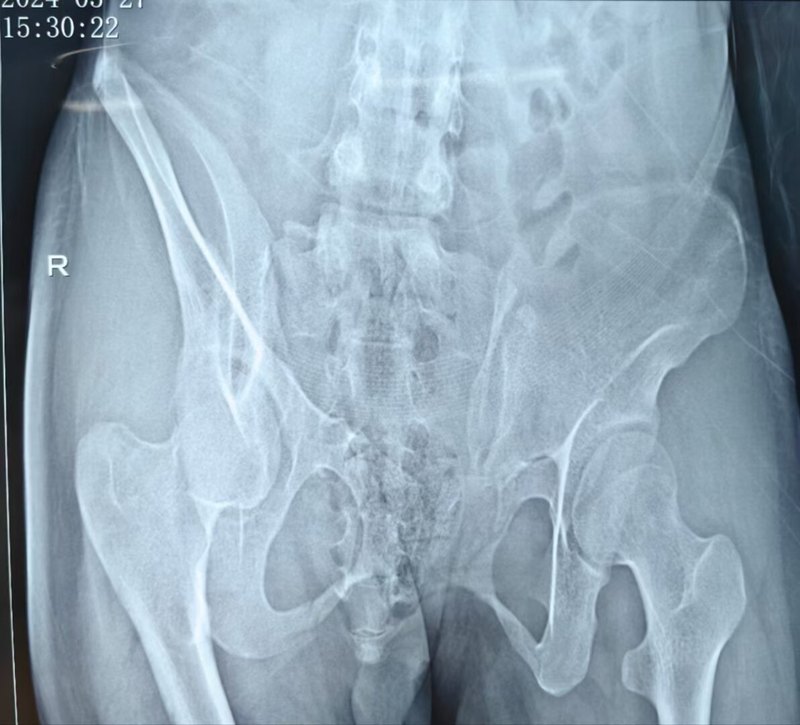

骨盆骨折1

嚴重的骨盆骨折會造成骨盆內(nèi)臟器的損傷,例如直腸的破裂損傷,膀胱損傷,尿外滲,如果有大的血管損傷,大出血死亡,空氣進入靜脈造成“氣栓”不給你救治的機會很快就會死亡,如果出現(xiàn)脂肪栓塞也是要命的并發(fā)癥。2015年10月25日我接診的這個病人,這個傷者處于昏迷狀態(tài)不知道名字,病歷登記叫“無名氏”。沒有親人和朋友隨行。必須緊急手術(shù),一秒也不能耽擱,手術(shù)知情同意書簽字是我和急診科主任簽字,承擔(dān)一切責(zé)任。這個傷者能夠救治成功,并且沒有功能障礙,欣喜之余將它記錄下來。手術(shù)前的骨盆三維成像。第一次手術(shù)就是胸腔閉式引流術(shù)和骨盆骨折開放止血內(nèi)固定,輸液、輸血等抗休克治療。其它部位的骨折二期完成。追蹤遠期治療結(jié)果。請轉(zhuǎn)發(fā)!作者:熊皓,副主任醫(yī)師。